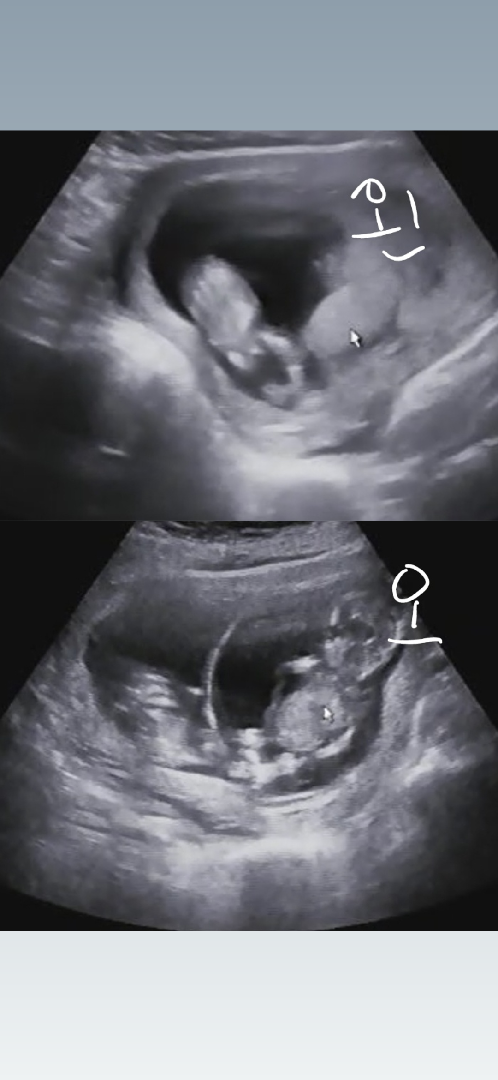

남매 아닐까요?왼: 남자/ 오:여자

쌍둥이 다리사이 봐주세용ㅜ

12주3일차에 찍은 초음파에요 두아이 사이가 너무 좋은지 같은위치에있어 선둥이가 정해지지 않았어용 왼쪽아이 오른쪽아이 둘다 정확하게 보이질않아서 동영상 집중해서 보다 찾은건데 어때보이시나용?

계속 움직이기도하구ㅜㅜ 자르고 편집해서 더 그런가봐용ㅠ 둘다 다리쪽만보이게 캡쳐한거라🥲🥲